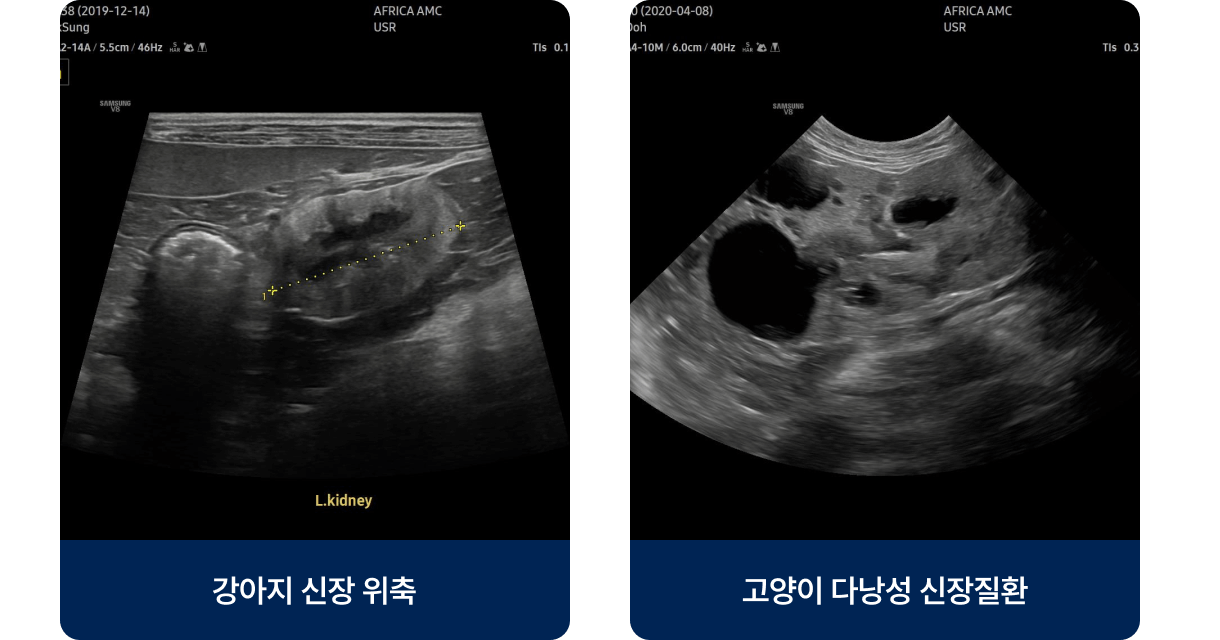

신장의 여과 기능이 점차 감소해 노폐물과 수분 조절이 제대로 이루어지지 않는 질환으로, 주로 중·노령견 및 노령묘에게 많이 발생합니다. 노화, 유전, 고혈압, 탈수, 만성 염증 등이 주요 원인이며 초기에는 물을 많이 마시고 소변량이 늘어나는 정도지만, 진행되면 식욕 저하·구토·입 냄새·무기력 등의 증상을 보입니다.